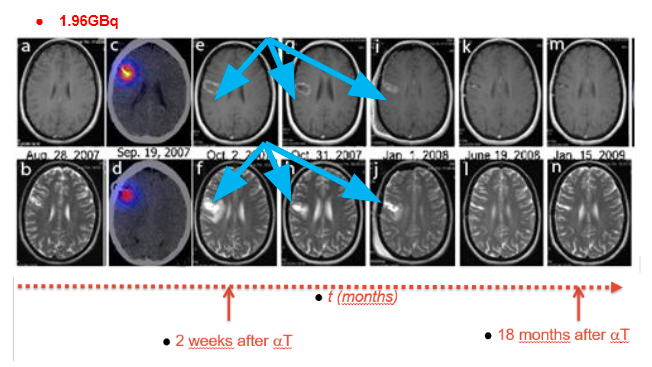

Waterfall diagram of survival times from 20 patients treated in Warsaw with Bi-213 DOTA Substance P. Red: total survival times since diagnosis (median 23,5 months); Violet: survival times following start of alpha therapy (median 10,9 months)

Subgroup analysis for inclusion criteria: definition of target population for phase III study Best results obtained in patients if tumor diameter ≤ 5 cm and Karnofsky score ≥ 70 Total survival times in subgroup: 33,75 months Survival times after start of alpha therapy: 27,8 months